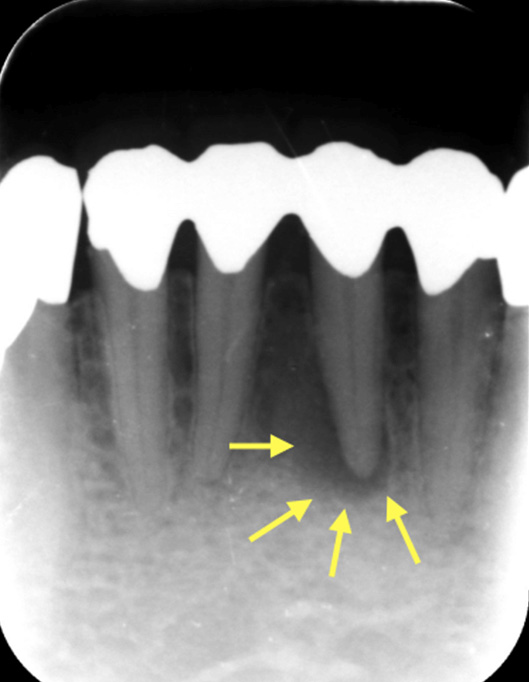

図2もともと根管治療をしたことのない歯で、

むし歯が進んで感染やひどい炎症を起こした場合

歯の根の回りが黒くなっているのが分かる。根の中の感染が原因で歯を支える骨を溶かしている。